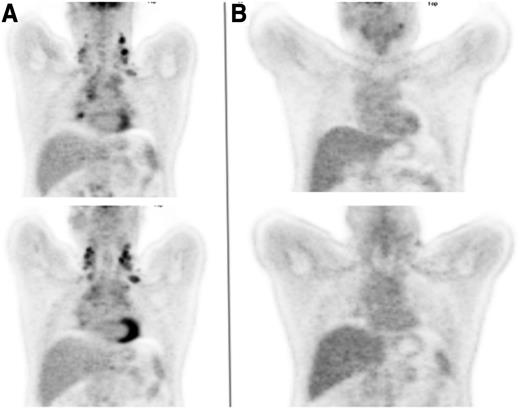

A 45-year-old man presented with progressively increasing breathlessness, a dry cough, drenching night sweats, and significant weight loss. Physical examination identified enlarged lymph nodes in both sides of the neck and both supraclavicular fossae. A chest radiograph showed widening of the mediastinum, which a computed tomographic (CT) scan confirmed as being the result of lymph nodes of maximum diameter 12 cm, accompanied by small pleural effusions, enlarged aortocaval nodes, and a focal defect in the spleen. Hemoglobin was 114 g/L, total white cell count was 9.2 × 109/L, lymphocyte count was 1.0 × 109/L, erythrocyte sedimentation rate was 48 mm/h, albumin was 31 g/L, and β2-microglobulin was 3.1 mg/L. A biopsy from one of the cervical nodes demonstrated grade 2 nodular sclerosing Hodgkin lymphoma. An FDG-PET scan (Figure 1A) demonstrated increased uptake in bilateral cervical, supraclavicular, mediastinal, subcarinal, paraesophageal, paraaortic and aortocaval nodes, as well as a focus of uptake in the left iliac bone, which had not been noted on the CT scan.

Coronal FDG-PET images of the thorax. (A) Prior to initiation of therapy and (B) following 2 cycles of ABVD.

The importance of these findings is that they suggest that it may be possible to start with the less toxic ABVD and expose only the minority of patients for whom this is unlikely to be curative to the more intensive BEACOPP regimen. This will need to be confirmed by longer follow-up of the studies, but many centers, our own included, now carry out an interim FDG-PET scan after 2 cycles of ABVD and will intensify treatment on the basis of a persistently positive result. This was the case for the patient described, whose interim PET scan showed persistent (grade 4) FDG uptake in the left cervical nodes, with lower-level uptake in the mediastinal, paratracheal, and subcarinal nodes (Figure 1B). He went on to receive 4 cycles of BEACOPP-14 after which the scan became negative, and his treatment was completed with 2 further cycles. He has remained in remission since the completion of BEACOPP-14, 4 years ago.